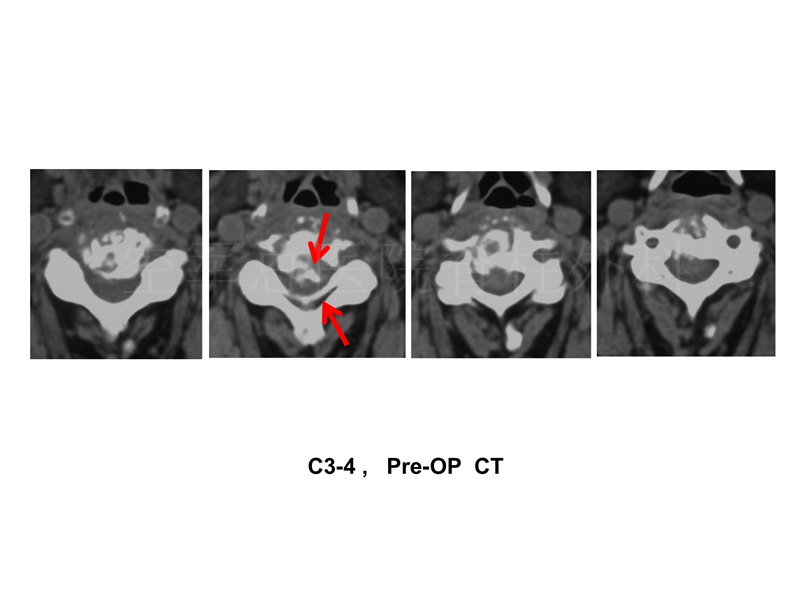

影像检查:

查体:颈3-4棘突压痛(+);双上肢、胸2以下、双下肢、会阴区感觉减退,右侧为著;双上肢肌力0-I级,双下肢肌力II-III级;双上肢腱反射活跃,双下肢腱反射减弱;Hoffmann(-),巴氏征(+),髌、踝阵挛(-);JOA评分1分。

刘宝戈教授:患者高龄84岁,根据临床表现、影像及化验指标诊断锁定结核。高位瘫痪,病程进展快,无论手术与否,其瘫痪加重、甚至死亡的风险都极高。因此需和家属沟通是否行手术治疗,如家属要求保守治疗,则安心卧床、制动、抗涝治疗即可。若选择手术,则需进行完整的麻醉评估,一定需行术前胸部CT检查,了解患者肺功能状态及是否有肺内活动性结核,若肺功能欠佳或有肺内活动性结核,则只能保守治疗。若评估可耐受麻醉,则首选前路手术,控制手术时间尽量在2小时以内,降低高龄患者麻醉风险及术后瞻望的可能性。选择切除颈3-4受感染侵及的椎体,行钛笼自体髂骨植骨,为防止因老年女性骨质疏松钛笼塌陷,钛笼上下端需加用终板盖。

党耕町教授:对于本例高龄老年颈椎感染病例一定要考虑到两点:第一,就是对于她来讲,救瘫痪就是救命。高龄,高危瘫痪,一旦丧失下地活动能力,呼吸肌功能受损,则卧床并发症很快出现。患者在一月前还能生活自理,因此应积极手术,抢救瘫痪。第二点,就是患者的骨质状况,颈3、4病灶还有无健康的骨组织。这涉及手术病灶清除的范围及重建方式的选择。结核引起瘫痪的原因有四点:1.脓肿 2.病理骨折 3.脊髓血管缺血 4.脊髓结核。本病例考虑为1、2为主,颈3有骨折后方脱位的表现。手术治疗前是不是可以考虑牵引,或者尝试牵引脊髓压迫就明显解除从而避免手术,都是值得考虑的方向。